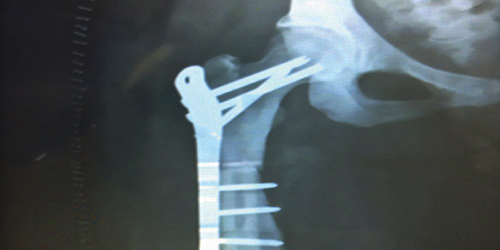

وكانت المريضة راجعت المستشفى تعاني من كسر بأعلى عظم الفخذ وتحت مفصل الفخذ وتحتاج لإجراء عملية جراحية استغرقت ثلاث ساعات لتثبيت الكسر بواسطة صفيحة معدنية وبراغي وتعاني من تصخر العظام وهذا النوع من الحالات تكون العظام شديدة الصلابة وسهلة الكسر مع عدم وجود نخاع عظمي مما يؤدي إلى إنيميا شديدة ونقص في الصفائح الدموية وحدوث نزيف وعدم تجلط الدم ونظرًا لطبيعة العظام وصعوبة الحالة والمضاعفات التي من الممكن حدوثها أثناء وبعد العملية فقد تم تحويل الحالة إلى عدة مستشفيات وتم الاعتذار عن الحالة.

وبعد مراجعة المستشفى قام الفريق الطبي بمعاينة الحالة، وتم إجراء العملية بنجاح ولله الحمد دون حدوث أي مضاعفات.